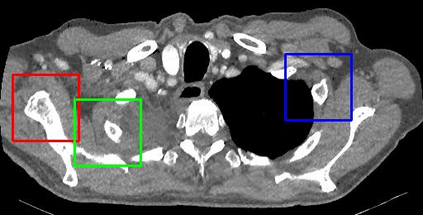

Due to the constraints of the imaging device and high cost in operation time, computer tomography (CT) scans are usually acquired with low intra-slice resolution. Improving the intra-slice resolution is beneficial to the disease diagnosis for both human experts and computer-aided systems. To this end, this paper builds a novel medical slice synthesis to increase the between-slice resolution. Considering that the ground-truth intermediate medical slices are always absent in clinical practice, we introduce the incremental cross-view mutual distillation strategy to accomplish this task in the self-supervised learning manner. Specifically, we model this problem from three different views: slice-wise interpolation from axial view and pixel-wise interpolation from coronal and sagittal views. Under this circumstance, the models learned from different views can distill valuable knowledge to guide the learning processes of each other. We can repeat this process to make the models synthesize intermediate slice data with increasing inter-slice resolution. To demonstrate the effectiveness of the proposed approach, we conduct comprehensive experiments on a large-scale CT dataset. Quantitative and qualitative comparison results show that our method outperforms state-of-the-art algorithms by clear margins.